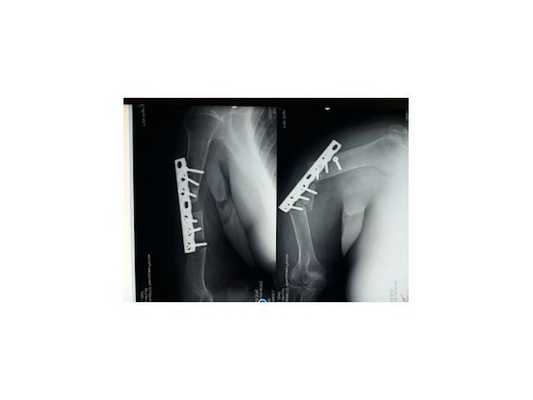

По данным рентгенографии: нестабильность остеосинтеза левой плечевой кости пластиной, диастаз (щель) между отломками.

Снимок через 3 года после травмы: полное сращение плечевой кости и перестройка трансплантата из гребня подвздошной кости